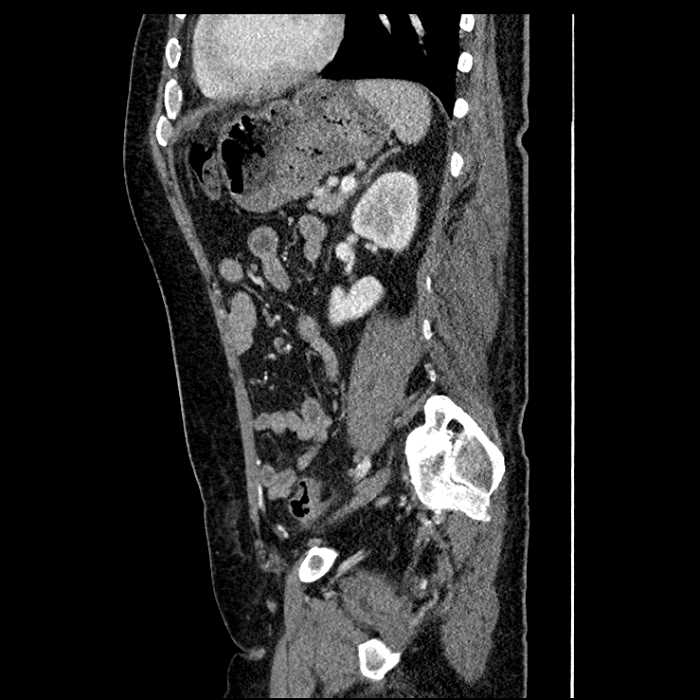

• Large fluid density structure in hepatic segments 7 and 8 measuring 10 x 7 x 7 cm with internal septation and circumferential ill-defined low density compatible with edema

• Peripherally enhancing subcapsular collections along the anterior margin of the left hepatic lobe measuring 3 x 1 cm and 2 x 1 cm

• Clearly marginated fluid density structure in segment 7 and several other scattered tiny hypodensities, which likely represent cysts

• Mild mural thickening of a segment of the sigmoid colon with adjacent fat stranding and a 1.5 cm fluid and gas collection along the tip of an inflamed diverticulum

• Loss of the normal fat plane between this collection and adjacent loops of small bowel, which demonstrate mural thickening

• No bowel obstruction

• Hepatic abscess

Acute sigmoid diverticulitis complicated by a small contained perforation and a large abscess in the right hepatic lobe. Additional small subcapsular abscesses along the anterior margin of the left hepatic lobe.

Additionally, loss of the normal fat plane between the peridiverticular collection and adjacent thickened loops of small bowel raises the potential for an enterocolonic fistula.

• The classic CT imaging appearance is a double target sign with internal low density surrounded by an internal enhancing rim (capsule) and a low density external rim (edema)

• Abscesses may be unilocular or multilocular

• Gas is present in a minority of cases

Hepatic abscess showing the double target sign with low density internally surrounded by a thin inner enhancing rim (red arrow) and ill-defined outer low density rim (yellow arrow). Blue arrow indicates an internal septation. Red arrows: additional smaller subcapsular abscesses. Red arrow: focal contained perforation associated with diverticulitis.